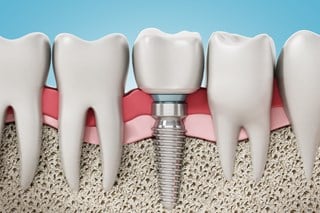

Nedan finns en lista med behandlingar som vi utför. Klicka på knapparna för att läsa mer om just den behandlingstypen🦷